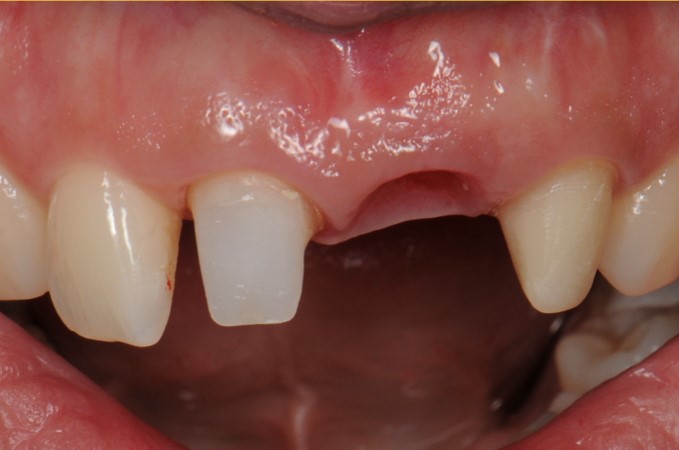

case6 症例(前歯部インプラント+ホワイトニング)

治療前

| 費用(税込み) | インプラント:550,000円、ホワイトニング:22,000円 |

| メリット・デメリット | デメリット 骨を削る必要がある |

| 治療回数 | 5-6回(根管治療はなし) |

| 主訴 | 差し歯が取れた |